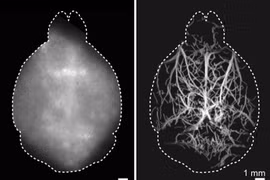

(khoahocdoisong.vn) - Các nhà nghiên cứu từ Đại học Zurich và ETH Zurich (Thụy Sĩ) đã phát triển một kỹ thuật mới cho phép chụp ảnh huỳnh quang vi mô ở mức gấp 4 lần giới hạn độ sâu do khuếch tán ánh sáng áp đặt.